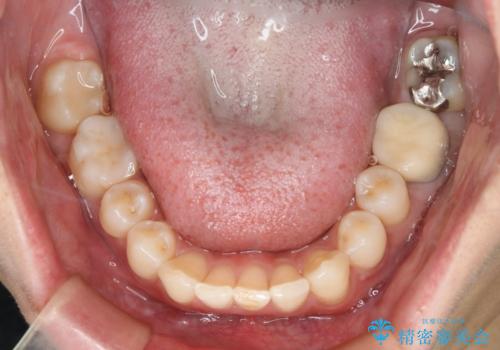

- 右上下6番の銀歯のやり変えを希望された患者様です。

切削量・形態を考慮し、上はセラミッククラウン、下はセラミックインレーでの治療を選択しました。

下はクラウンほど切削量が多くないと判断し、インレーでの治療を選択しました。